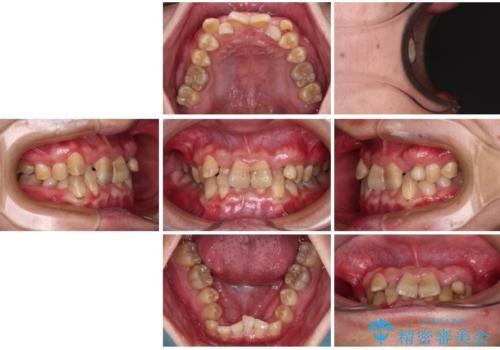

- 上下の前歯のデコボコを改善したいと来院された患者様です。

上顎の歯列幅が狭く、それによって歯が並ぶスペースが不足しています。

また下顎の歯列幅も制限され、内側に歯が倒れています。

それらを改善するため上顎に拡大装置を用いて、審美装置にてワイヤー矯正を行いました。

左上の乳犬歯は当初保存する計画でしたが、虫歯が大きいため抜歯になり、患者様の希望によりブリッジにしました。

上顎が側方に拡大されて歯が並ぶスペースを確保できました。

それに伴い下顎の歯列も拡大され、舌側に倒れているのが改善されました。